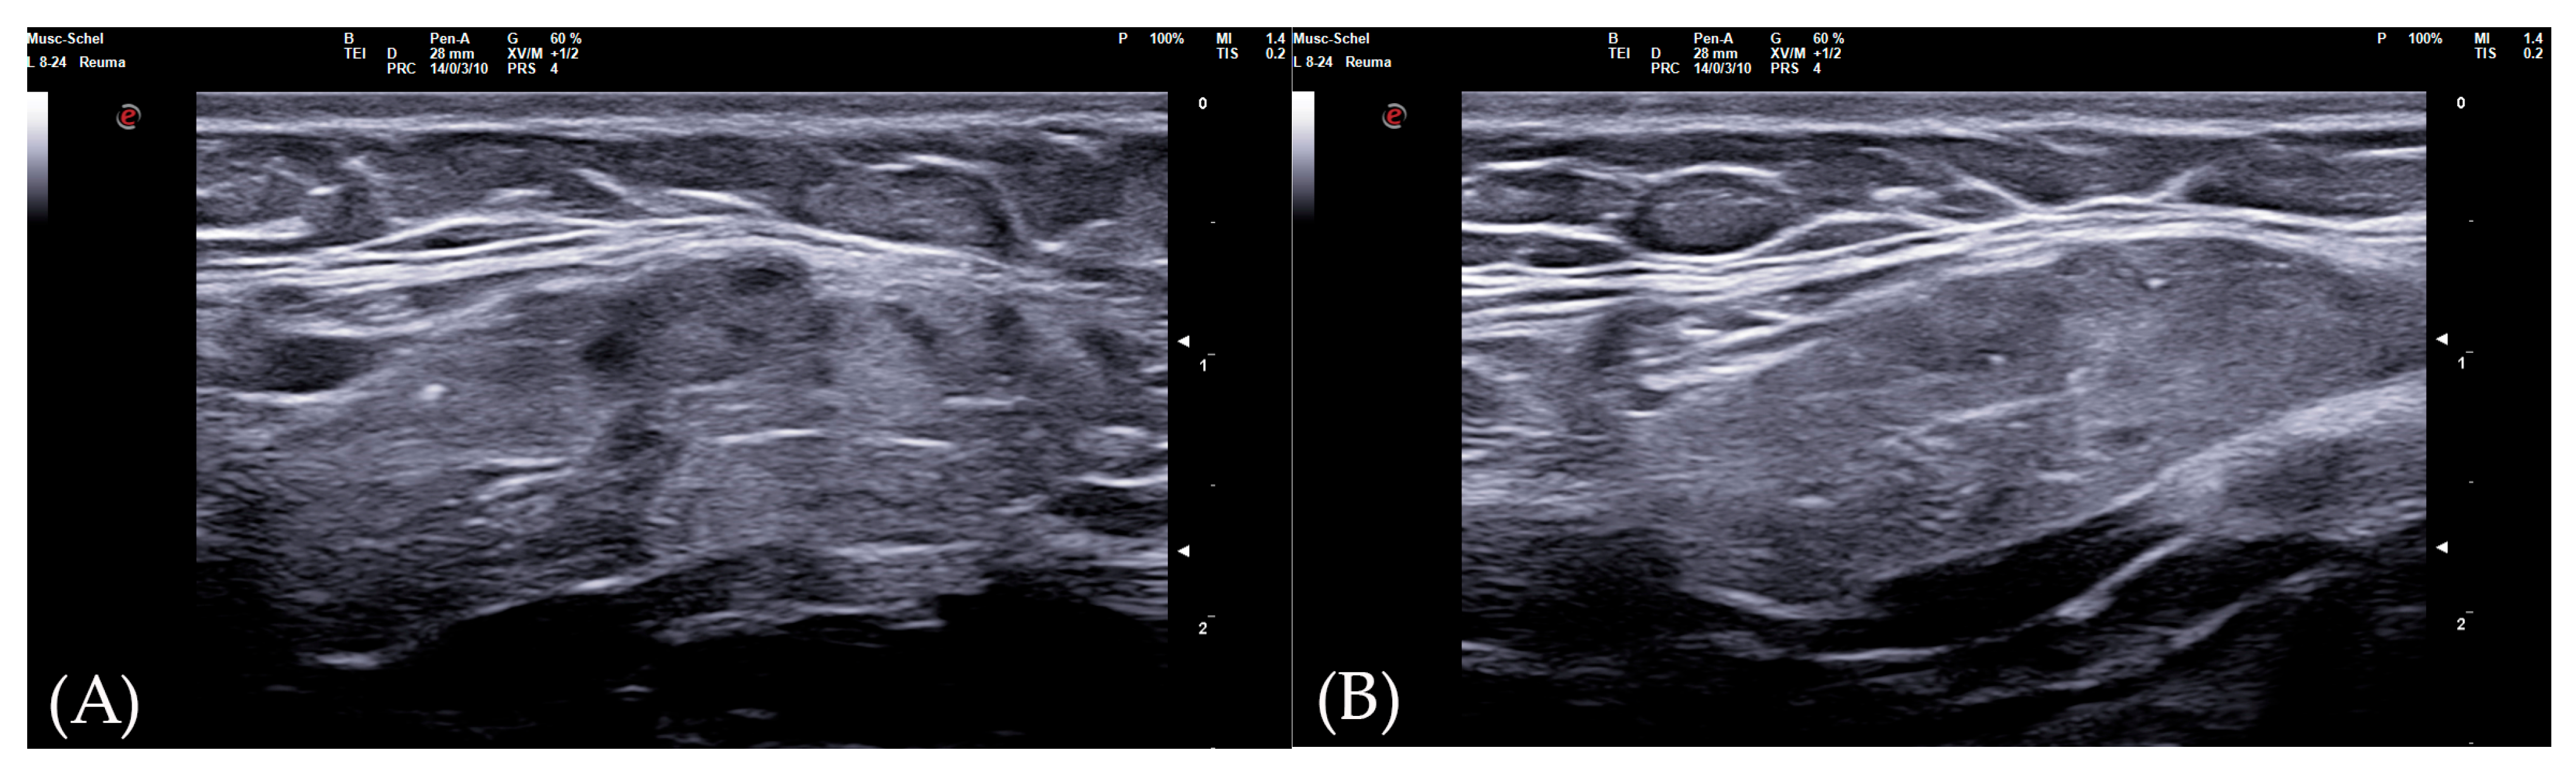

The 0–3-graded OMERACT score was used to assess the ultrasonographic structure of each gland [13,14,15]. The score was applied on each gland, and defined as follows: Grade 0, normal parenchyma (sono-structure comparable to the thyroid gland); Grade 1, mild inhomogeneity without anechoic or hypoechoic areas and hyperechogenic bands; Grade 2, moderate inhomogeneity with focal anechoic or hypoechoic areas; and Grade 3, severe inhomogeneity with diffuse anechoic or hypoechoic areas occupying the entire gland surface [13] (Figure 1).

Figure 1. Parotid SGUS score 3 in primary Sjogren syndrome. Female 51-year-old patient with sicca syndrome, positive Schirmer test, positive autoimmunity (ANA+, Ro-SSA+), positive labial biopsy for SS. A coronal trasverse scan over left parotid (4–15 MHz linear probe) shows diffuse inhomogeneity with hypo-anechoic areas occupying the entire gland volume, surrounded with septal echoic thickening and scanty normal parenchymal tissue (SGUS-OMERACT score = 3).